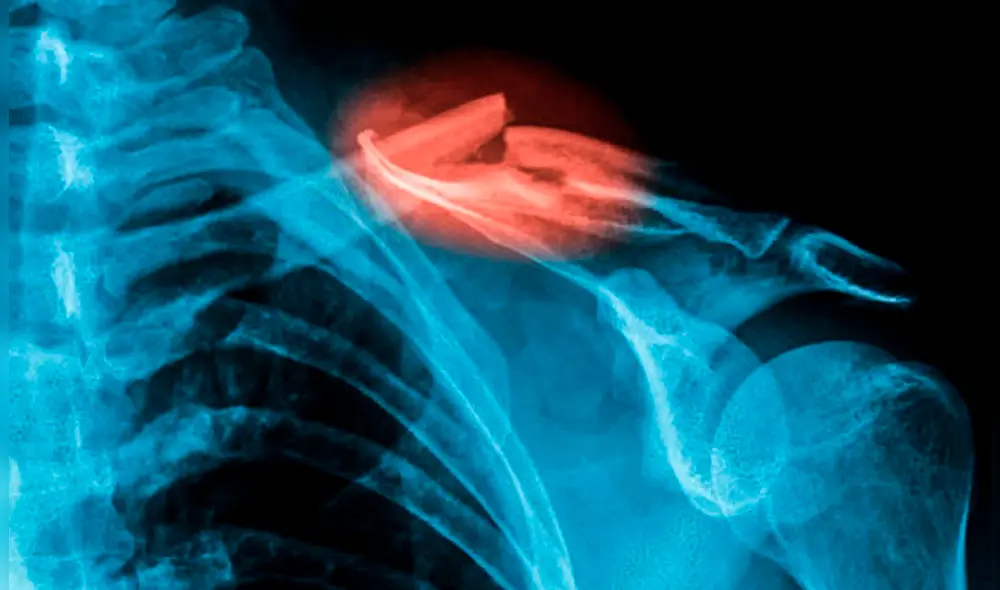

Investigadores desarrollaron una innovadora pistola de pegamento capaz de imprimir en 3D un material similar al hueso, ofreciendo una solución prometedora para la reparación de fracturas durante las cirugías. Modificando un dispositivo estándar, esta tecnología permite aplicar el material directamente sobre las fracturas, lo que podría transformar los procedimientos quirúrgicos.

Las primeras pruebas, realizadas en conejos, demostraron su efectividad, especialmente en fracturas irregulares, donde los métodos convencionales resultan más complejos de aplicar. Con su potencial para mejorar la precisión y la eficacia de las reparaciones óseas, esta pistola de pegamento 3D podría cambiar el futuro de la medicina quirúrgica.

Gracias a esta innovadora técnica, los investigadores lograron imprimir injertos óseos directamente sobre fracturas y defectos óseos durante intervenciones quirúrgicas en conejos. Este avance, como destacó el coautor del estudio, Jung Seung Lee, no solo acelera el tiempo de operación, sino que también aumenta la eficiencia en condiciones quirúrgicas reales.

En un experimento realizado con conejos blancos de Nueva Zelanda, los investigadores evaluaron la efectividad de los injertos óseos impresos en 3D al compararlos con el tratamiento tradicional con cemento óseo. Tras reforzar las fracturas con placas metálicas y tornillos, rellenaron los defectos óseos de los conejos con su filamento especial o con el cemento convencional, y luego monitorearon la evolución de los animales durante 12 semanas.

Los resultados mostraron que los conejos tratados con el injerto óseo impreso en 3D experimentaron una mejor regeneración ósea, con un tejido más denso y una formación ósea más robusta en comparación con los que recibieron el tratamiento tradicional. Al finalizar el estudio, el material experimental mostró una degradación de solo un 10%.